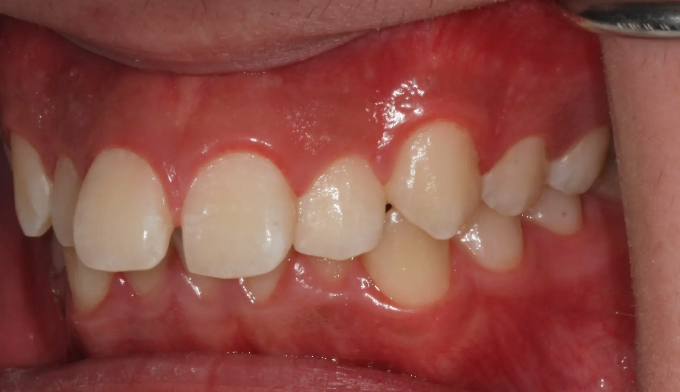

앞니가 돌출되어 있으면서 동시에 위 맨끝 어금니가 아래 어금니와 사선으로 물려있는 가위교합이 관찰됩니다.

가위교합은 음식물 섭취에 있어서도 비효율적이지만, 올바른 잇솔질을 하기가 어려워 구강위생에도 좋지 않아 교정이 필요합니다.

돌출입을 해소하고 동시에 가지런하지 못한 치열을 바르게 펴서 양치하기 좋은 상태로 만들어줍니다.